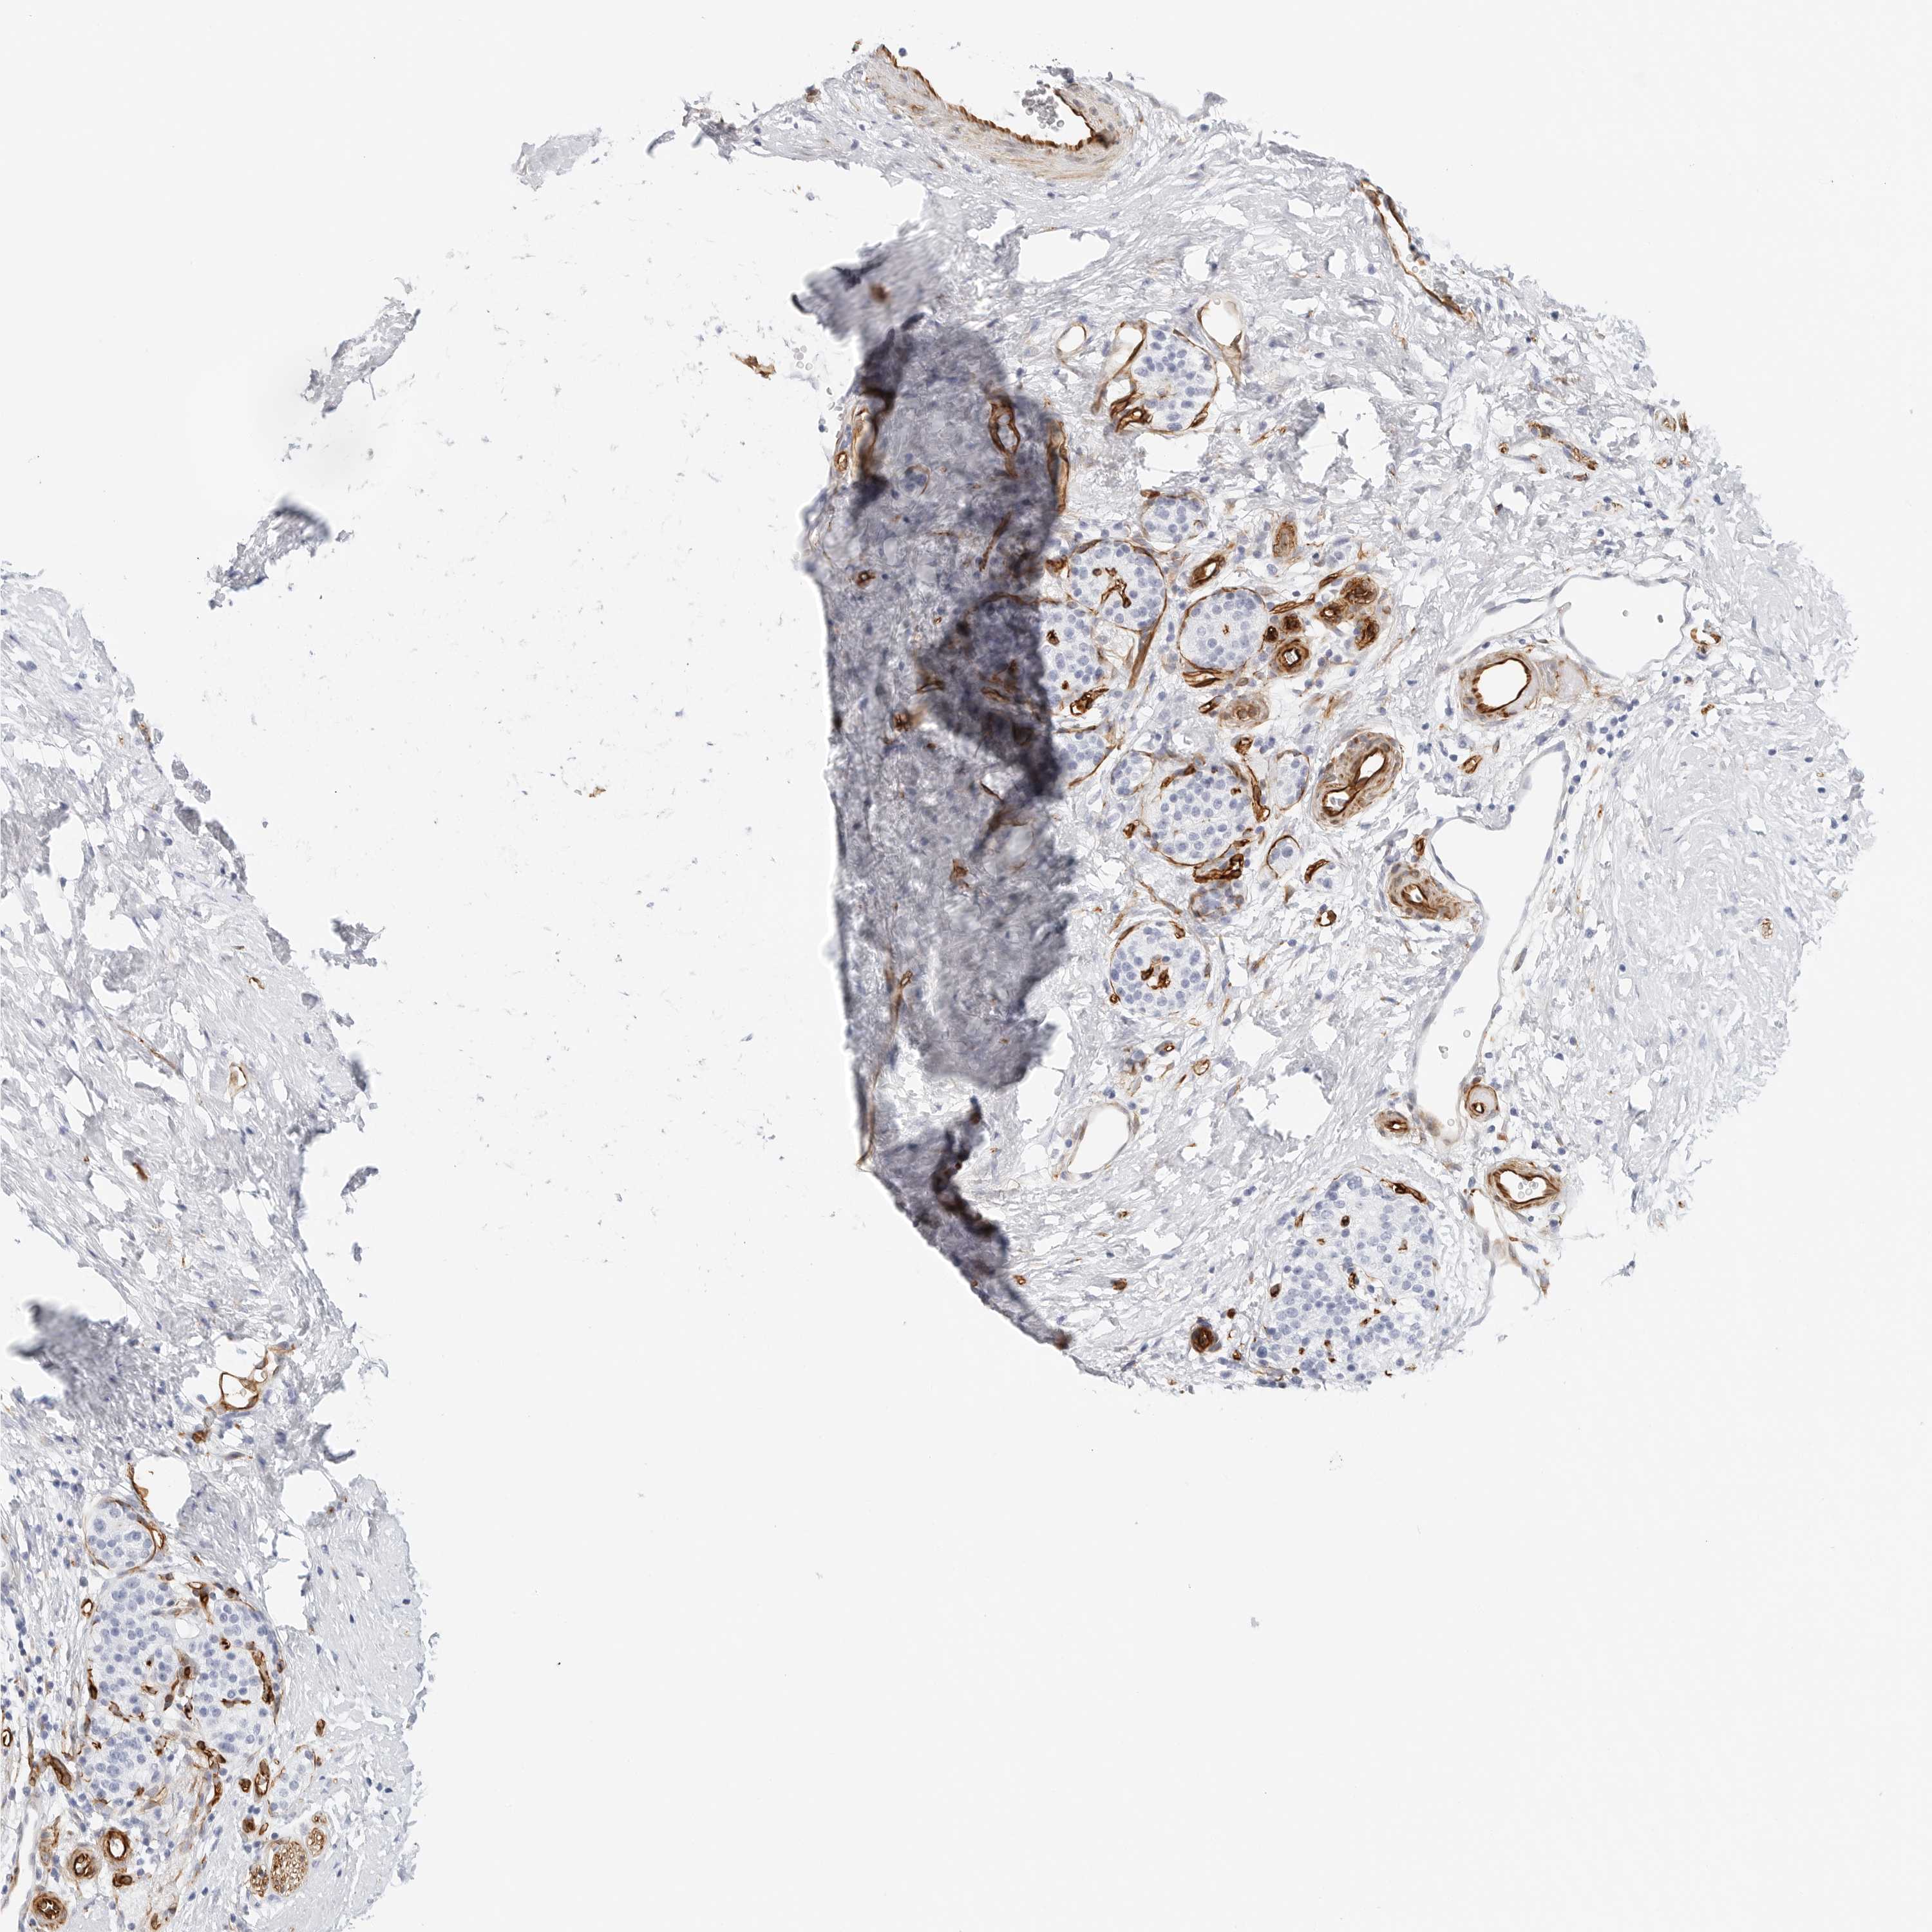

PANCREATIC CANCER - Protein expressioni

A mouse-over function shows sample information and annotation data. Click on an image to view it in a full screen mode. Samples can be filtered based on level of antibody staining by selecting one or several of the following categories: high, medium, low and not detected. The assay and annotation is described here.

Note that samples used for immunohistochemistry by the Human Protein Atlas do not correspond to samples in the TCGA dataset.

Antibody stainingi

Antibody staining in the annotated cell types in the current human tissue is reported as not detected, low, medium, or high, based on conventional immunohistochemistry profiling in selected tissues. This score is based on the combination of the staining intensity and fraction of stained cells.

Each image is clickable and will lead to virtual microscopy that enables deeper exploration of all samples and also displays staining intensity scores, fraction scores and subcellular localization as well as patient and tissue information for each sample.

Antibody HPA007007

Antibody HPA026111

Antibody CAB005889

Antibody CAB058692

Staining

High

Medium

Low

Not detected

Intensity

Strong

Moderate

Weak

Negative

Quantity

>75%

75%-25%

<25%

None

Location

Nuclear

Cytoplasmic/membranous

Cytoplasmic/membranous,nuclear

Adenocarcinoma, NOS

Adenocarcinoma, metastatic, NOS